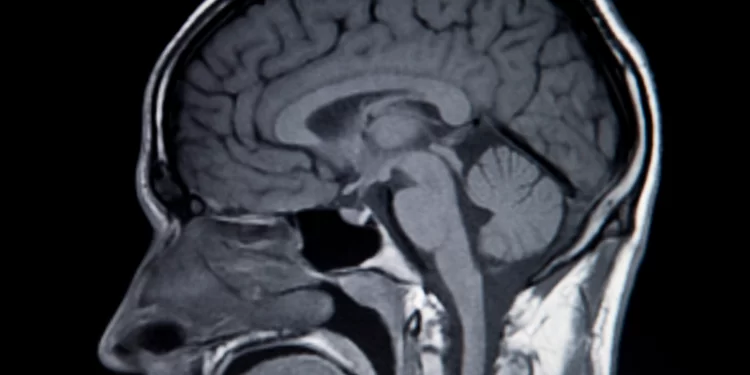

Cinco años después del inicio de sus síntomas, el participante se sometió a una cirugía para insertarle 256 electrodos de silicio, cada uno de 1,5 mm de longitud, en una región del cerebro que controla el movimiento. Maitreyee Wairagkar, neurocientífica de la Universidad de California en Davis y coautora del estudio, y sus colegas entrenaron algoritmos de aprendizaje profundo para capturar las señales cerebrales del hombre cada 10 milisegundos.